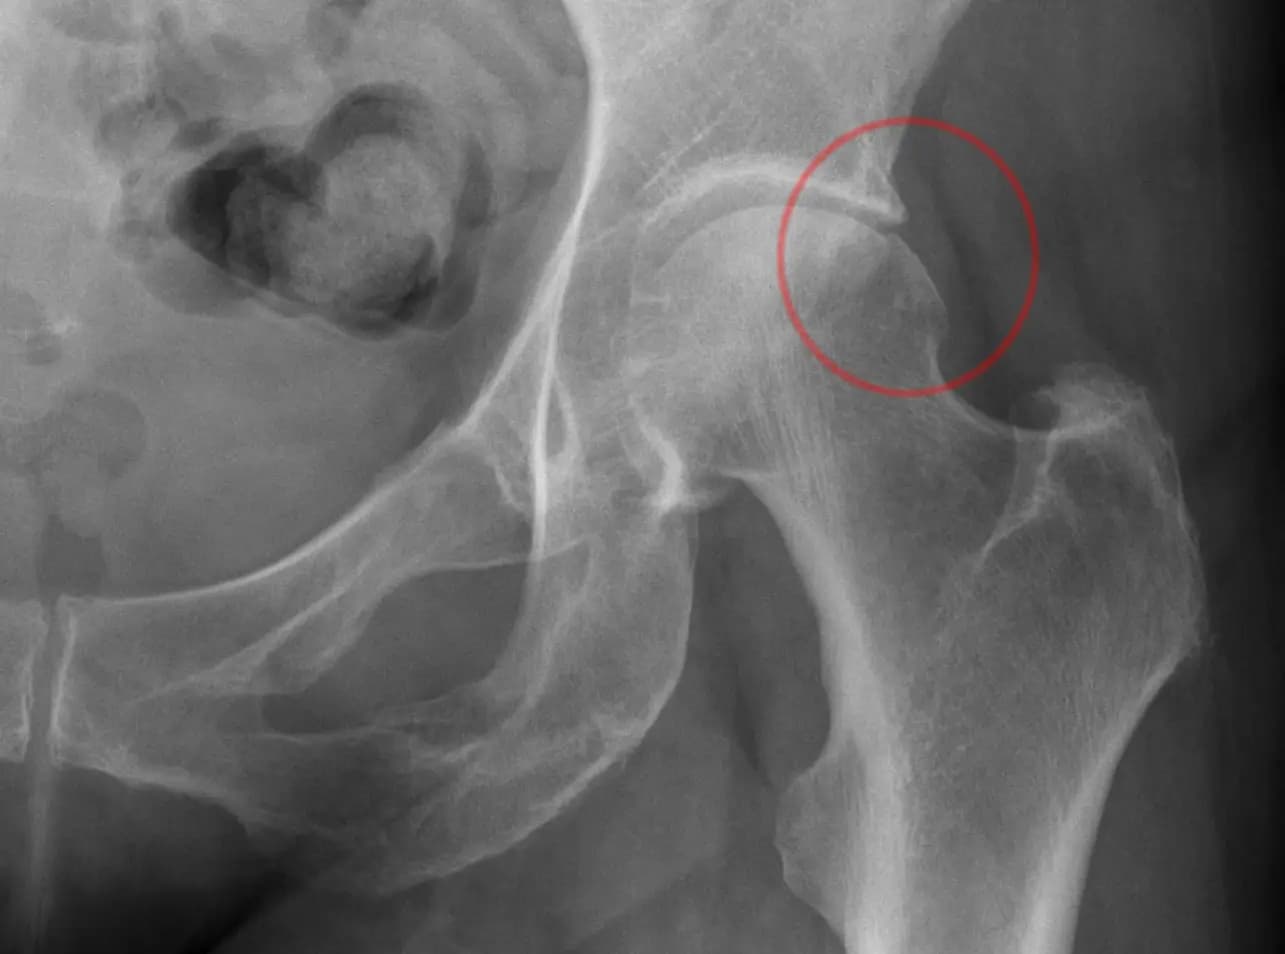

- Cam (CAM) tipi: Femur başı-boyun bileşkesi tam yuvarlak değildir; femur boynunda oluşan çıkıntı soket kenarıyla sürter. Bu durumda femur başı-soket arasında anormal temas olur ve kıkırdak hasarı gelişir.

- Röntgen (standart AP ve lateral): Kemik deformitelerini, alfa açısı ve soket örtüsünü gösterir.